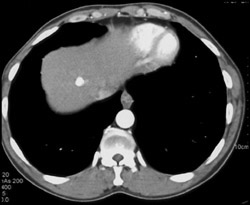

Esophageal Varices